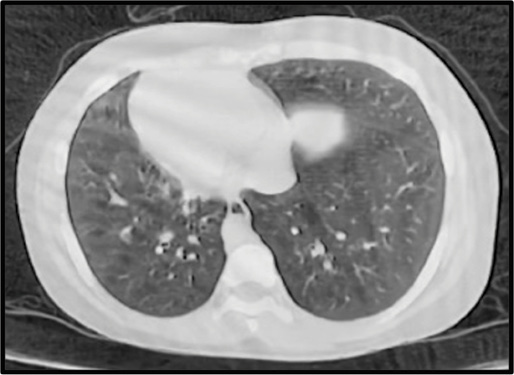

Se solicita radiografía de senos paranasales en la cual se observan niveles hidroaéreos en ambos maxilares sugestivos de senositis maxilar (Figura 1). Así mismo, se solicita tomografía pulmonar en la que se evidencia dextrocardia con imágenes de vidrio despulido y árbol en gemación. Por lo tanto, se realiza broncoscopia en que se observan cuerdas vocales con adecuada movilidad, sin presencia de secreciones. Se realiza toma de biopsia transbronquial y muestras de lavado bronquialveolar para su posterior análisis microbiológico, el cual reporta cultivo negativo. También se realiza gen expert para tuberculosis con resultado negativo. Con estos hallazgos clínicos y radiológicos se diagnostica a la paciente con un síndrome de Kartagener completo.

Figura 1.

(A) Radiografía de senos paranasales en proyección waters en la cual se observan senos maxilares con nivel hidroaéreo y velamiento perimetral. (B) Tomografía torácica ventana pulmonar, corte axial en la que se observa dextrocardia e imágenes en vidrio deslustrado y áreas de árbol en gemación ubicadas en la língula, (C) y (D) cortes coronales con imágenes de bronquiectasias cilíndricas para hiliares bilaterales (página siguiente).